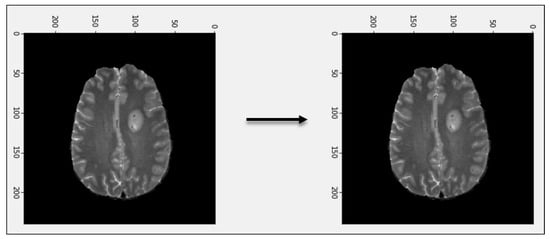

3.1. Pre-Processing

3.2. Tumor Identification